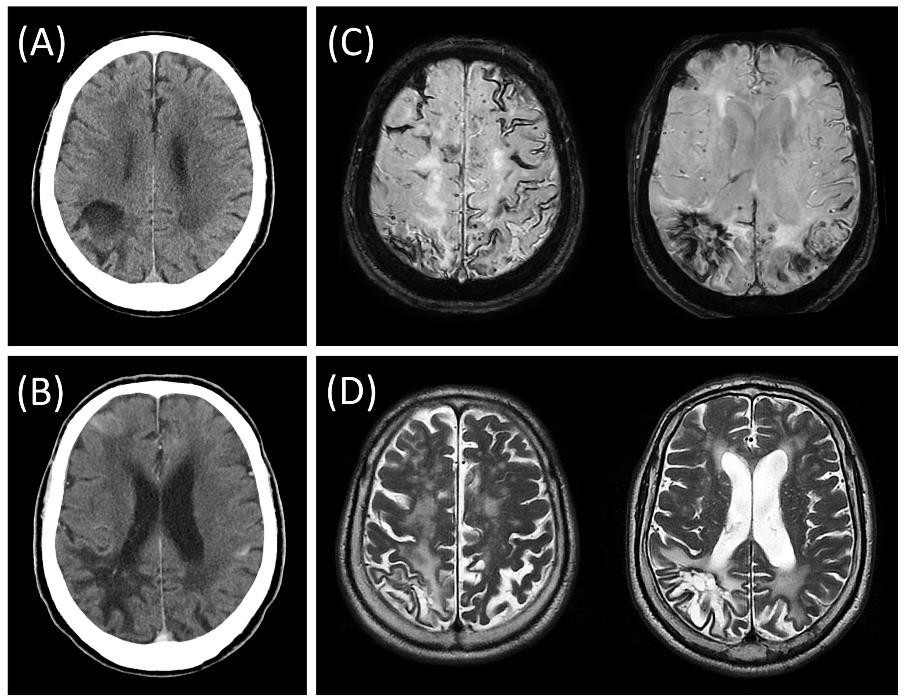

4. ábra. Új diagnosztikai entitások azonosítása CAA-RI-ben. (A) Egy CAA betegünknek a szuszceptibilitás súlyozott MRI szekvencián (SWI) látható vérzései környezetében a FLAIR felvételen a liquor jelintenzitása néhány barázdában megnőtt (sulcal non-nulling), ezen a területen a Gadolinium kontrasztos (T1Gad+) szekvencián kiterjedt lágyagyhártyai halmozás is jelen van. (B) Az eltérések 2 hónap alatt spontán elmúltak. (C) Fejfájáshoz és fokális epilepsziás görcstevékenységhez társulóan a lágyagyhártyai halmozás visszatért 4 hónappal később. (D) A halmozás és a tünetek nagy dózisú vénás szteroid terápiát követően ismét eltűntek. Tanulmányunk eredményei alapján a két jelenség fehérállományi ödéma nélkül is CAA-RI-re utal, a diagnosztikai kritériumok érzékenységét szignifikánsan növelik, valamint a terápiahatékonyság biomarkereiként alkalmazhatók.

Szalardy et al. 2024, Neuropathology and Applied Neurobiology nyomán.